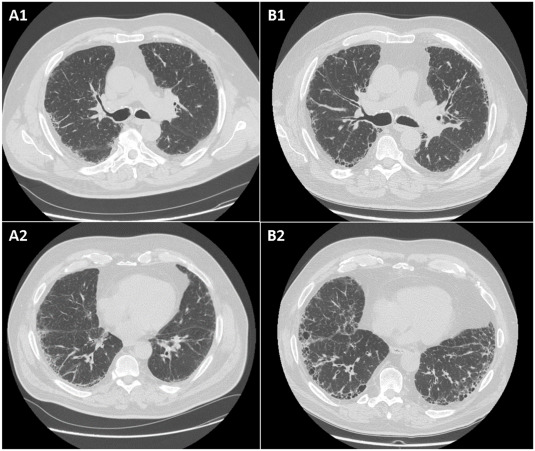

Sustained Impact of Dapagliflozin on Epicardial Fat Thickness in Type 2 Diabetes: Insights from the DAPAHEART 4-Year Experience